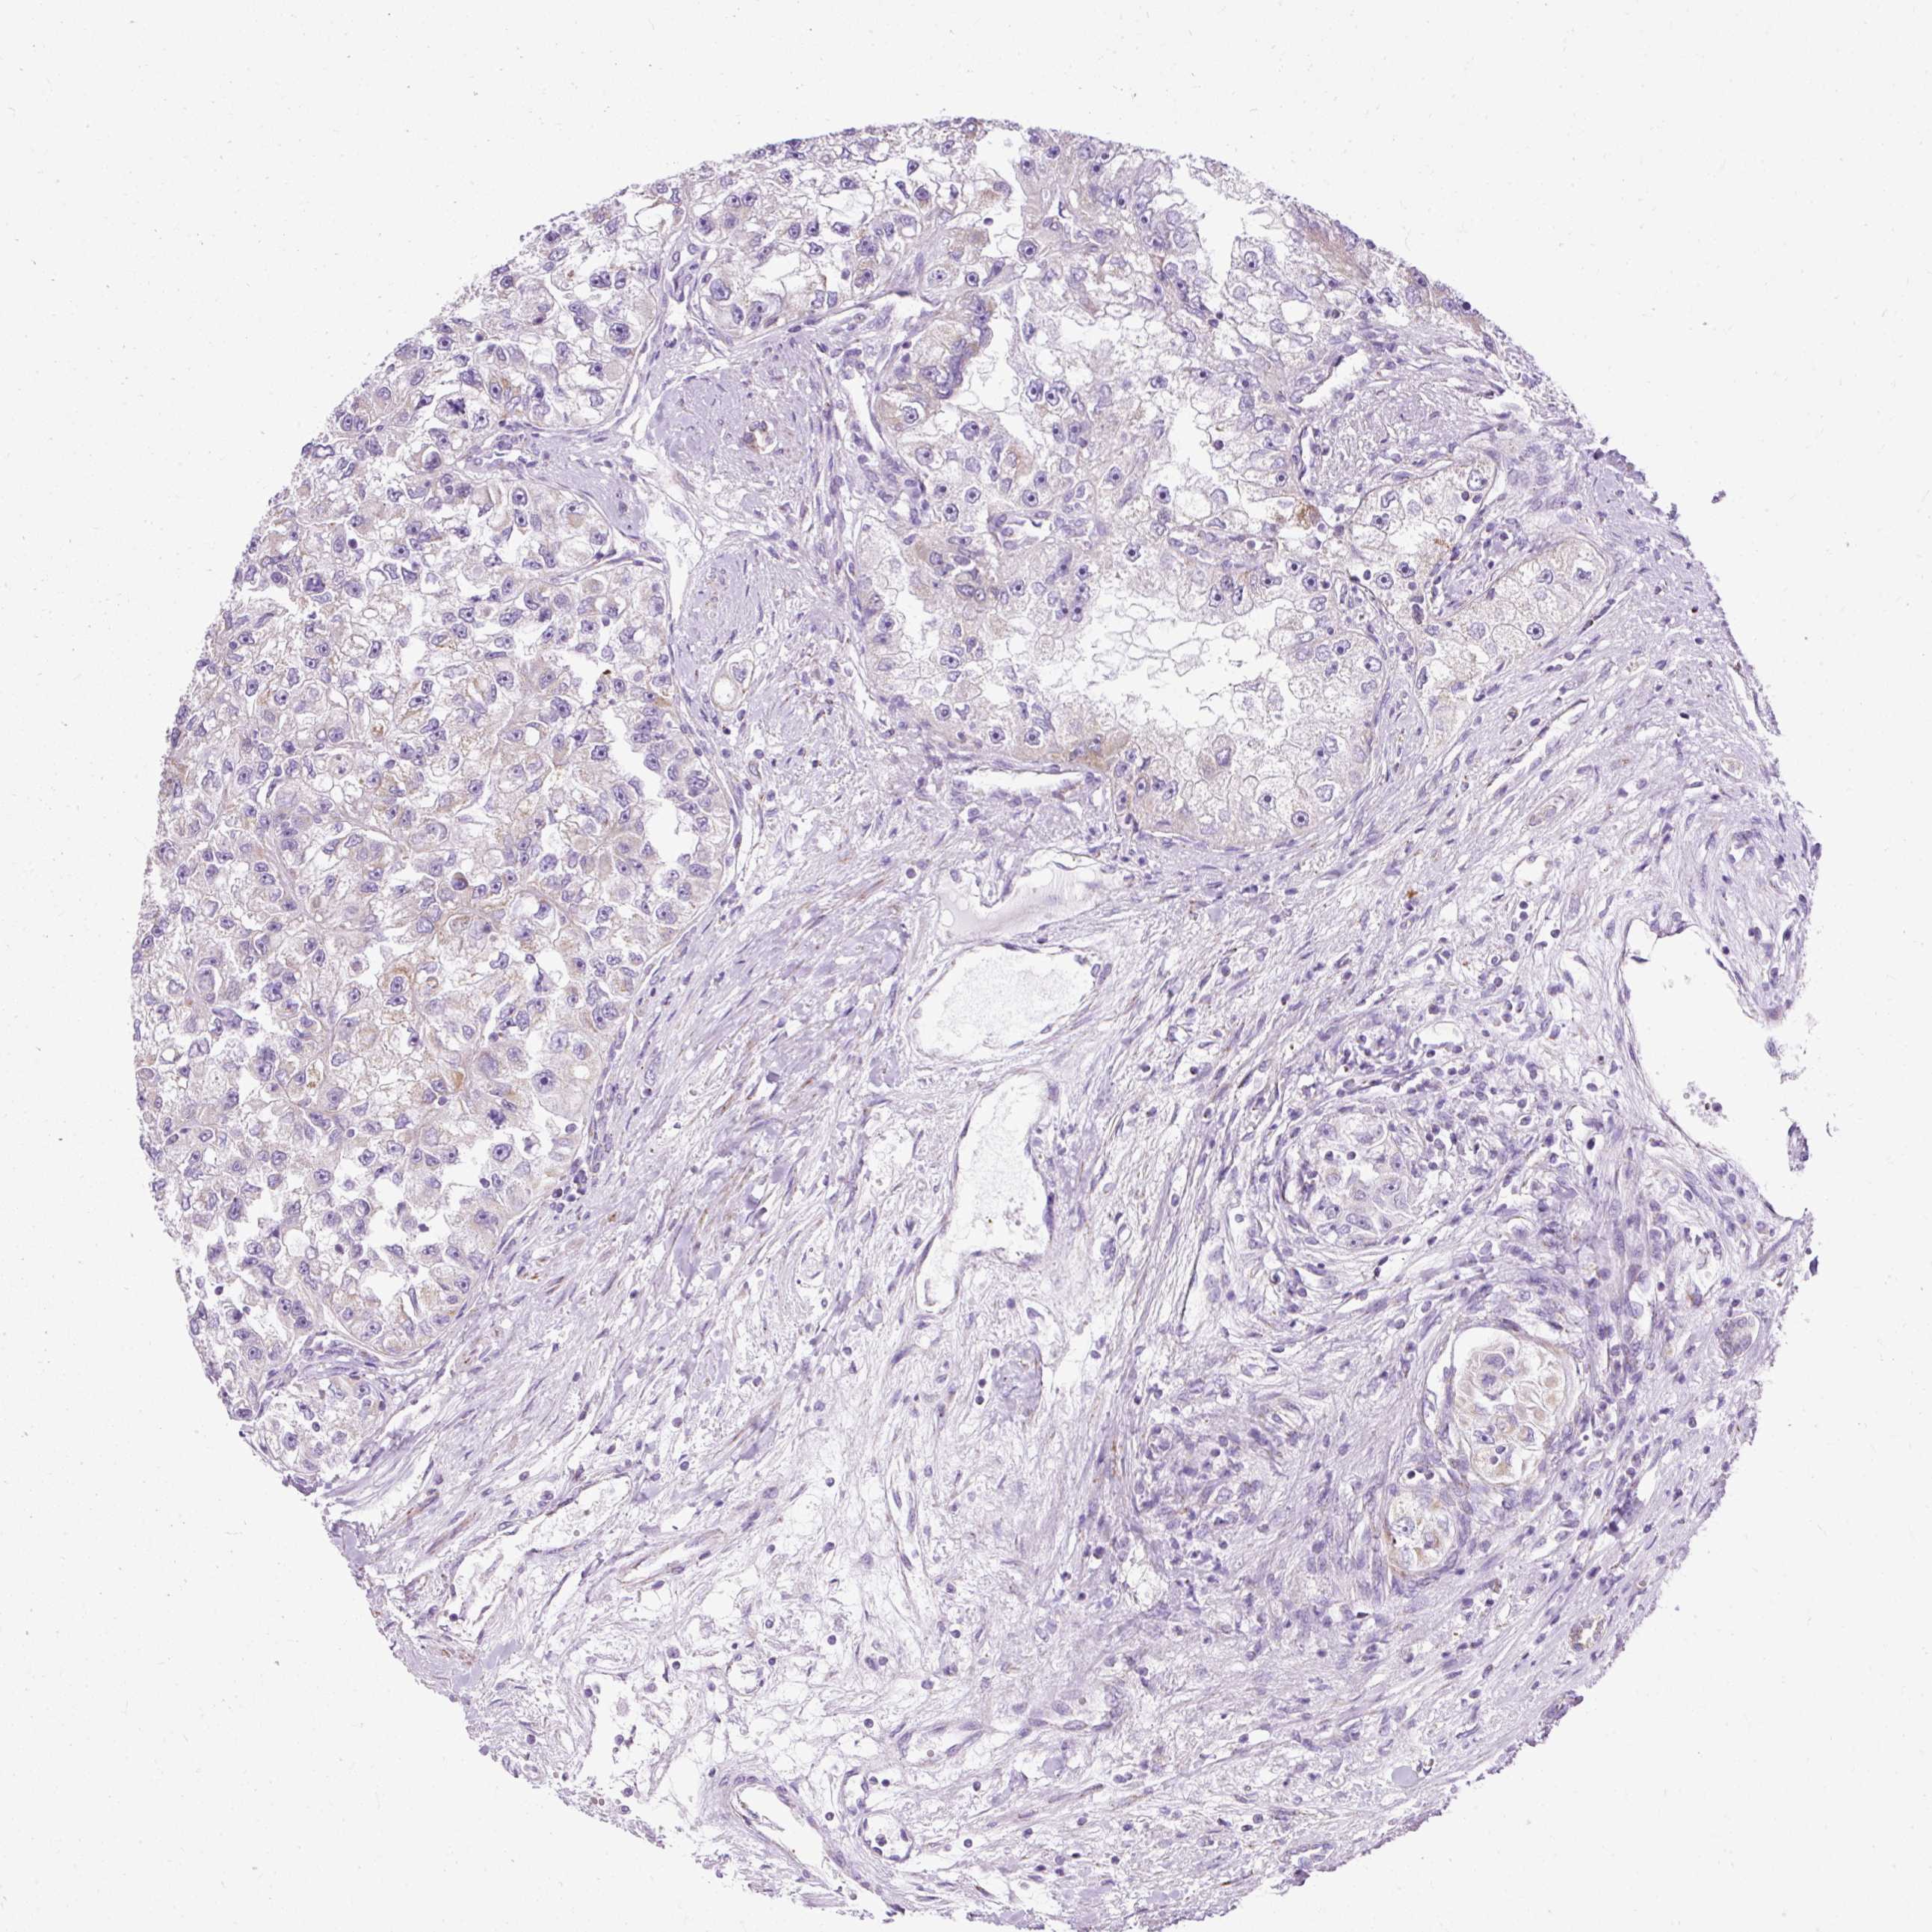

Renal cancer

Kidney renal papillary cell carcinoma